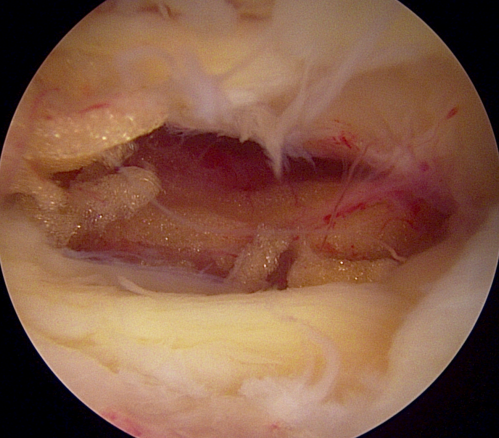

양방향 척추 내시경을 통한 다발성 척추 협착증의 치료 [온종합병원 척추센터 우영하 소장 ]

척추관 협착증은 척추관이 좁아지거나 협착되어 척수나 신경근을 압박하는 상태를 말합니다. 이런 경우, 양방향 척추 내시경이 매우 유용한 치료 수단이 될 수 있습니다.

- 계획: 양방향 척추 내시경은 미세한 카메라와 도구를 사용하여 척수와 주변 신경 구조를 정밀하게 시각화할 수 있습니다. 이를 통해 정확한 진단을 내릴 수 있으며, 각 환자에게 맞는 개별적인 수술 계획을 수립할 수 있습니다.

- 소형 절개와 미세한 수술: 양방향 척추 내시경은 작은 절개를 통해 수술을 수행할 수 있습니다. 이는 환자의 회복 기간을 단축시키고 합병증의 위험을 줄입니다. 또한, 미세한 도구를 사용하여 정교한 조작이 가능하므로 척추 근육과 조직을 최소한으로 손상시키면서 치료할 수 있습니다.

- 출혈 및 감염 위험 감소: 작은 절개와 정교한 수술 기술은 출혈 및 감염의 위험을 최소화합니다. 이는 환자의 안전을 높이고 수술 후 합병증의 가능성을 줄입니다.